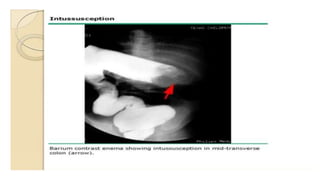

BARIUM ENEMA